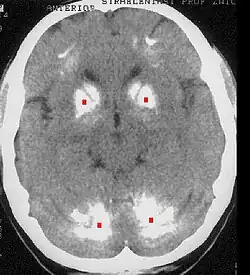

Die Fahr-Krankheit oder Morbus Fahr (auch striatodentale Kalzifikation oder Fahr-Syndrom) ist die Bezeichnung für eine Verkalkung der Basalganglien des Gehirns (genaugenommen für eine Kalzinose zwischen Corpus striatum and Nucleus dentatus), welche nicht auf arteriosklerotische Prozesse zurückzuführen ist. Die Erkrankung ist nach Theodor Fahr (1877–1945) benannt, der sie 1930 beschrieb. Die Namensgebung ist umstritten, da sie verschiedene Krankheiten vermischt.

Die Fahr-Krankheit kann idiopathisch sporadisch oder als familiär gehäufte Erkrankung auftreten, sowohl autosomal dominant als auch rezessiv vererbt. Symptomatisch kann es zum Morbus Fahr auch im Rahmen von Hypoparathyreoidismus und Pseudohypoparathyreoidismus kommen.

Als Zufallsbefund muss diese Basalganglienverkalkung bei jenen 40 % der Betroffenen bezeichnet werden, die keine Symptome aufweisen. Die Berechtigung als eigenständige Krankheit wird deshalb zum Teil auch bezweifelt.

Bei den symptomatischen Formen werden Kopfschmerzen, Sprachstörungen, eine langsam fortschreitende Demenz und extrapyramidale Symptome beschrieben. Eine Korrektur des Calciumspiegels kann letztere deutlich verbessern.[8]